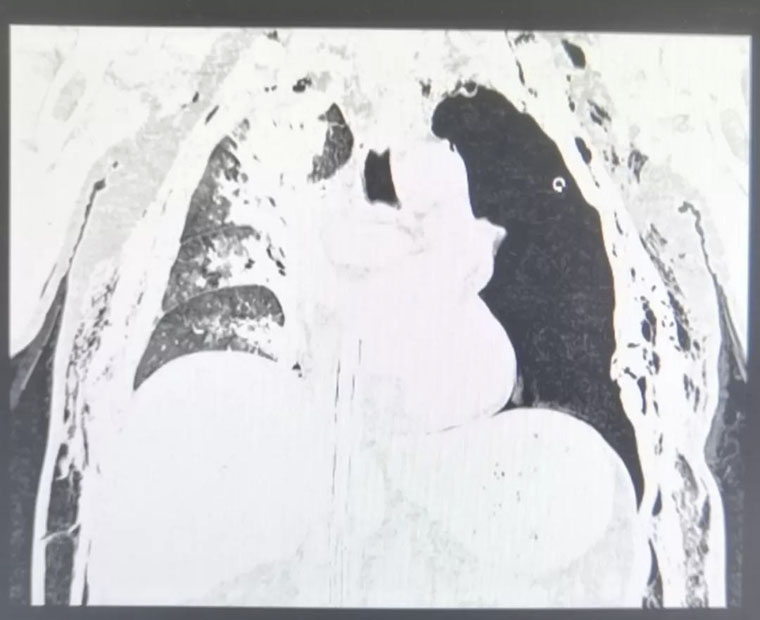

患者的胸部CT

然而,大量的气泡从胸腔闭式引流管喷出,我们意识到,这样下去肯定不行,带ECMO做CT检查,再次请胸外科会诊,讨论手术的必要性。